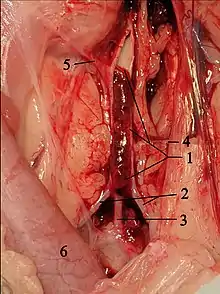

Saddle thrombus in the feline aorta. 1 opened Aorta with thrombus, 2 A. iliaca externa, 3 common trunk for both Aa. iliacae internae, 4 A. circumflexa ilium profunda, 5 A. mesenterica caudalis, 6 Colon descendens.